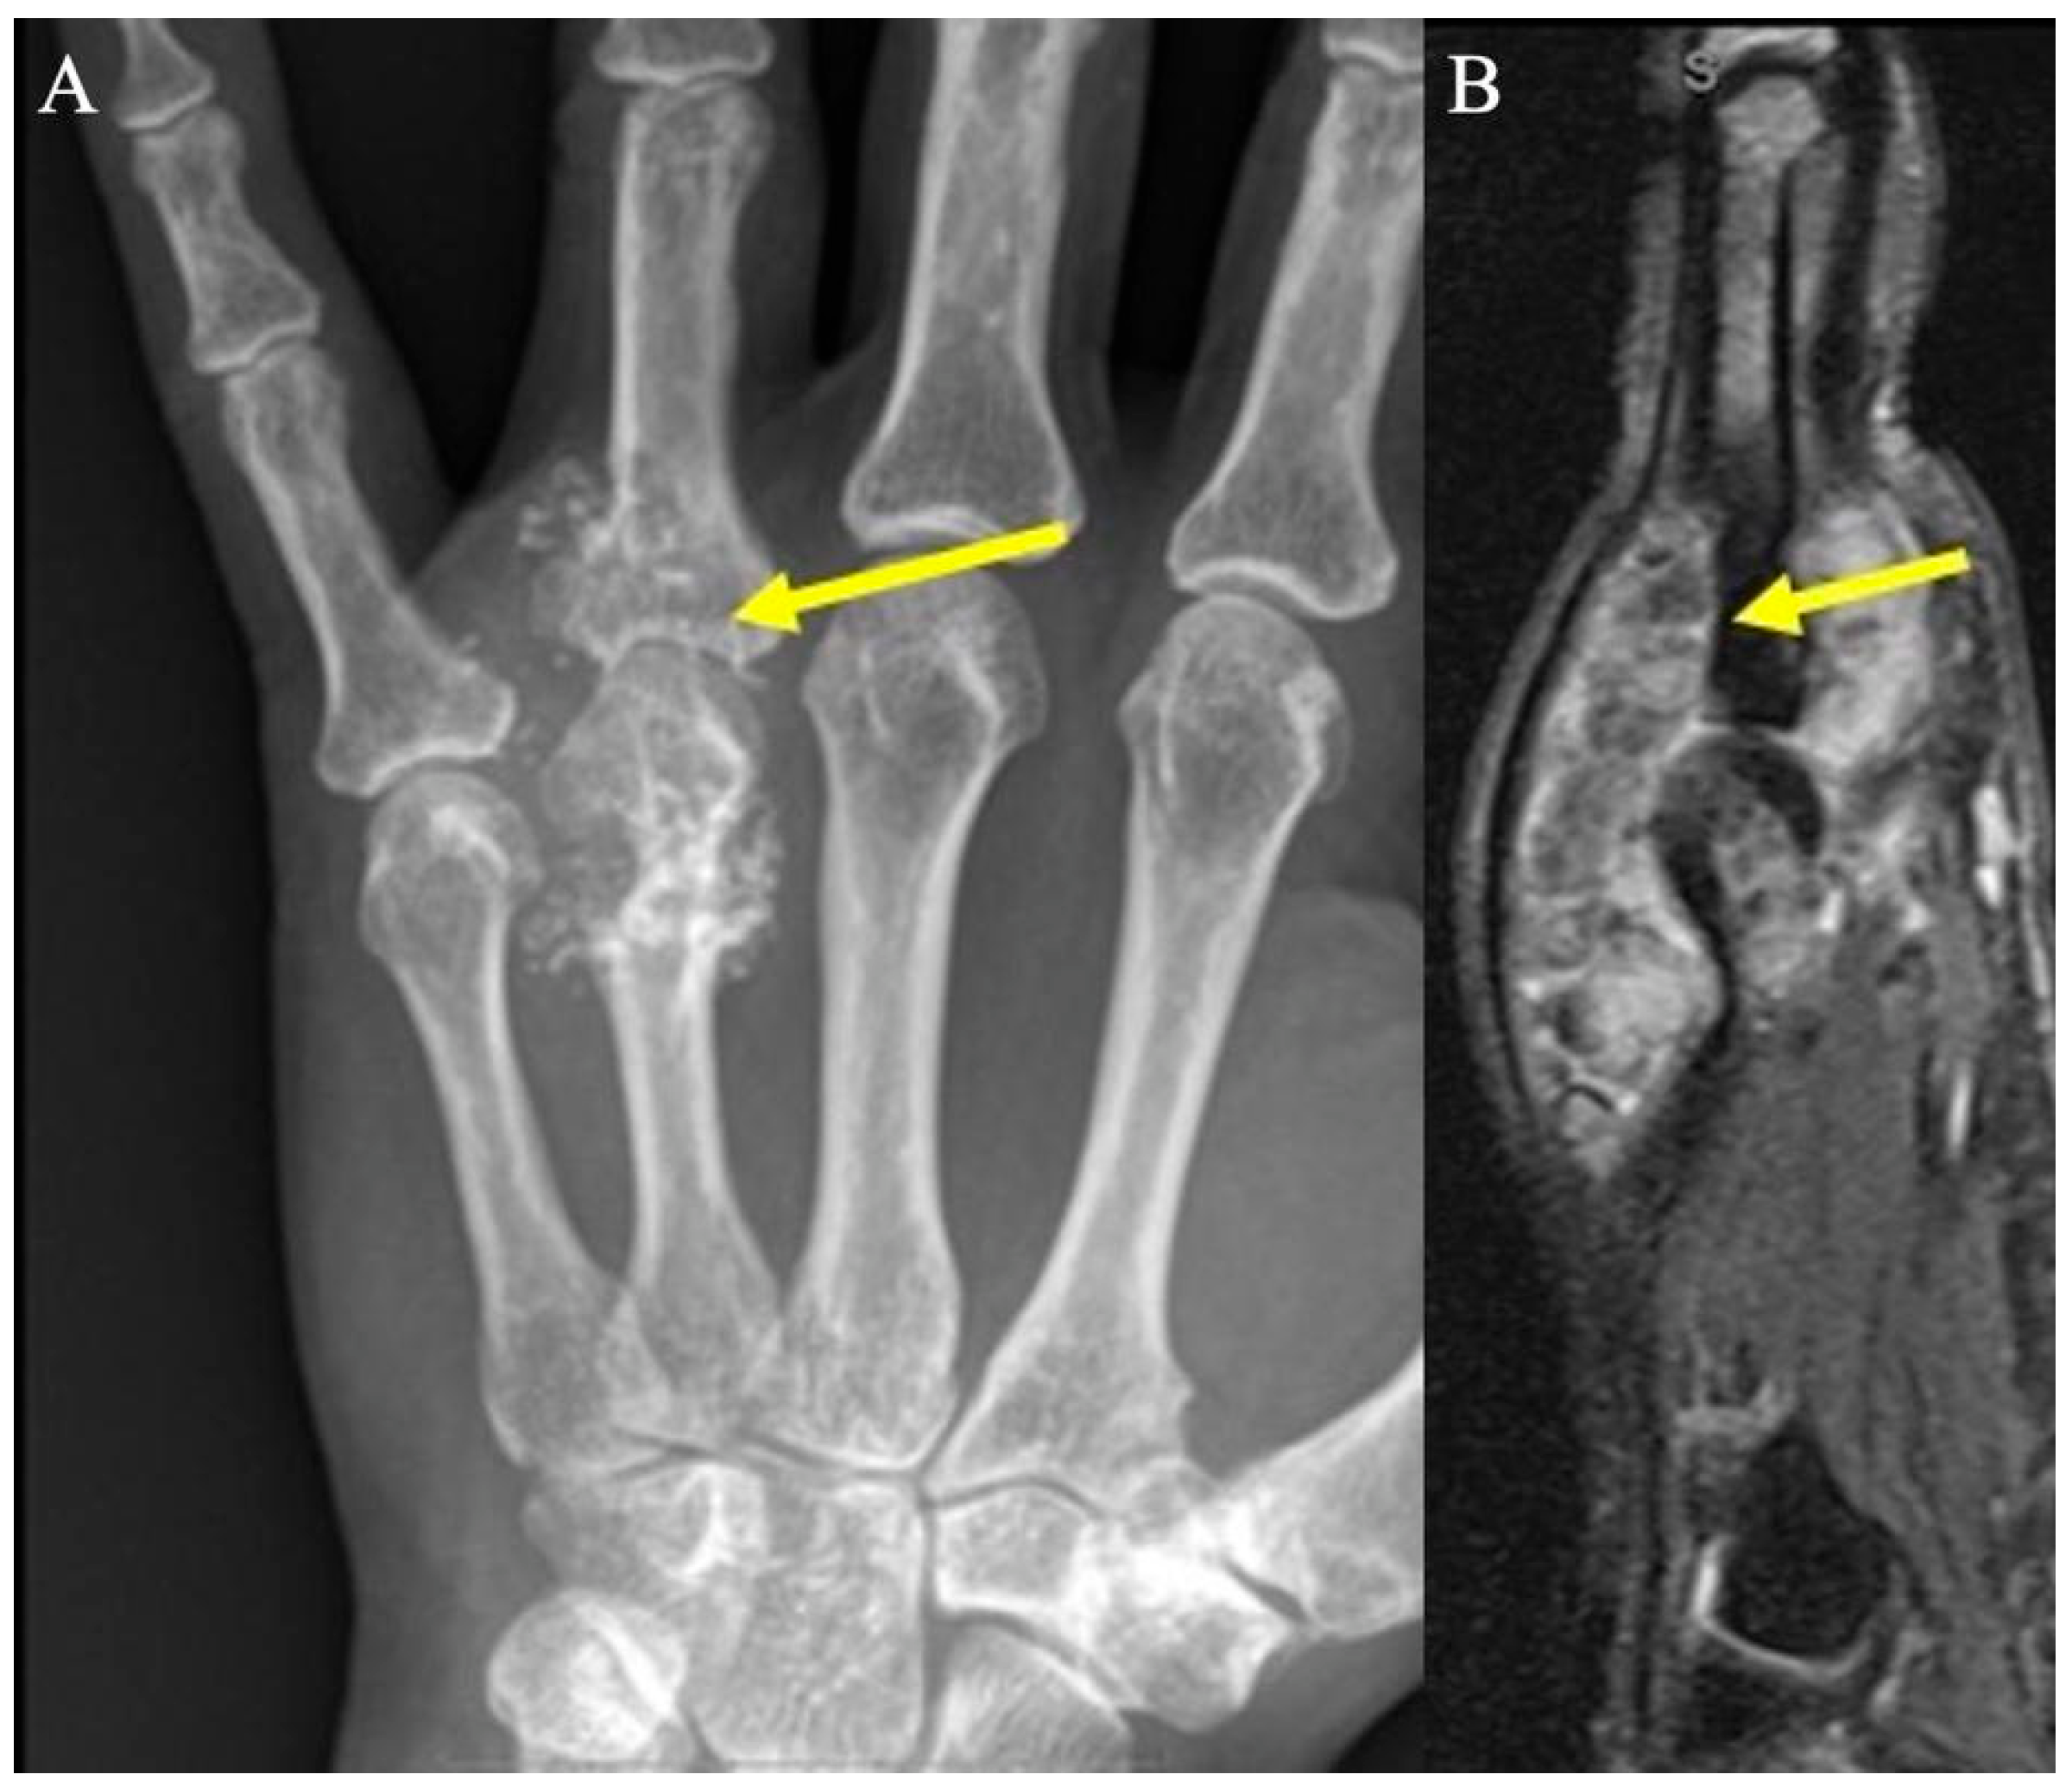

2.5. Glomus Tumors

2.5.1. Clinical Features

2.5.2. Imaging Appearance